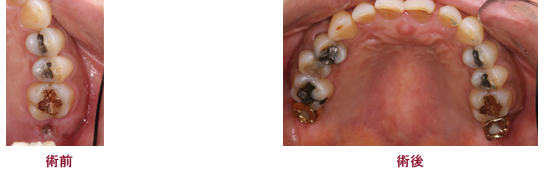

症例6

50代女性 歯肉を切らないインプラント治療

治療期間:3ヵ月

価格:34万円(かぶせもの含む)(税別)

- 治療内容

- 通常のインプラント埋め込みに比べ痛みが出にくい処置です。 顎の骨が平らな状況であれば処置が可能です。

- リスク

- 外科処置を伴います。

まれに体質に合わない(チタンと骨が癒合しない)方がいらっしゃいます。

フラップレスの場合は歯肉と骨が十分存在しないと成功率が低下するため、条件が良い場合にのみ適応が可能です。

※フラップレス手術1日後の状態 歯肉の治りが早く、縫わないで処置が可能